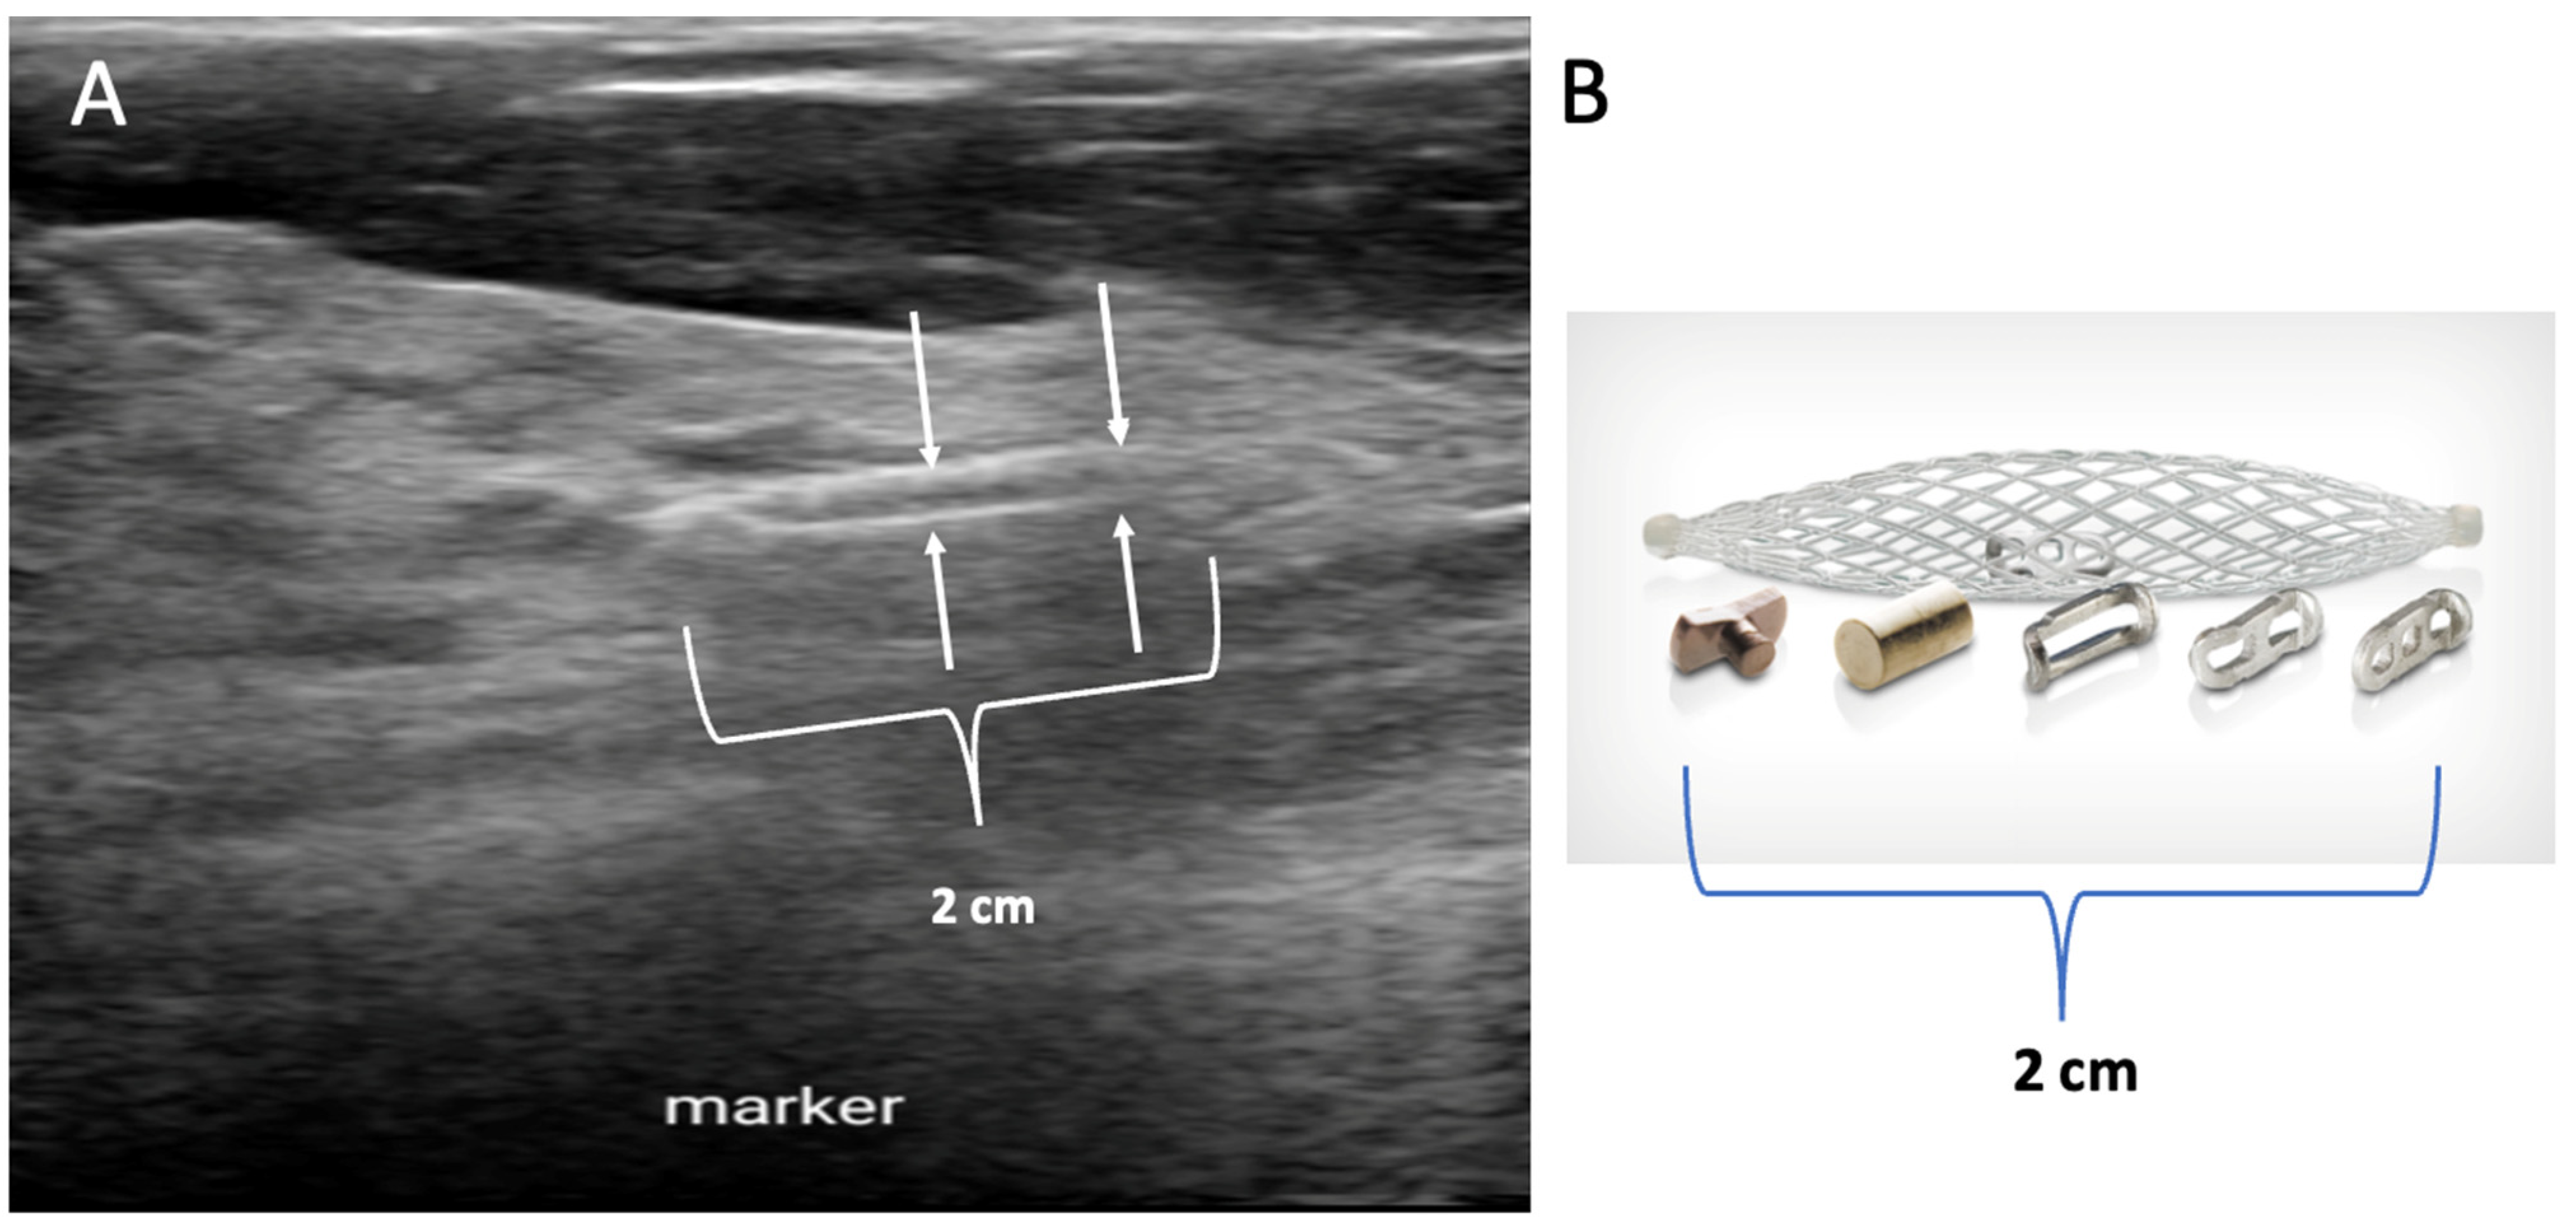

Placement of biopsy site marker(s). Regardless of cancer size, insertion of a biopsy site marker (also called a “clip” or “chip”) at the time of mammogram-, ultrasound-, or MRI-guided needle biopsy is recommended to document the site of the cancer. In situations where pre-cryoablation chemotherapy and/or anti-HER2/neu therapy is planned, insertion of a biopsy site marker prior to initiation of anticancer medications documents the location of the cancer in the event drug therapy-induced shrinkage of the cancer makes it difficult to detect by ultrasound (Figure 5).

Figure 5.

Mammogram performed before (A) pre-operative chemotherapy showing large, white, ultrasound visible cancer encircled by hash marks. After completing pre-operative chemotherapy, a repeat mammogram (B) of the same breast showed complete disappearance of the original cancer leaving only a circular metal biopsy site marker (arrow) to indicate the location of the original cancer.

Biopsy site markers come in many shapes and sizes, but most measure less than 10 mm in length. In breast radiology, the most commonly used biopsy site markers are metallic (stainless steel, titanium, or nickel) devices that are optimized for detection by mammography, but are poorly visible by ultrasound. However, several biopsy site markers have been optimized for ultrasound detection by encasement of the metallic component in a larger, absorbable collagen or hydrogel sleeve (Figure 6). For cancers that are already visible by ultrasound, the type of marker is unimportant as the tumor itself provides an obvious target for ultrasound-guided cryoablation. However, when the breast cancer is very small or invisible to ultrasound, insertion of an ultrasound-visible marker at the time of the initial needle biopsy or subsequently will facilitate ultrasound-guided cryoablation of ultrasound-occult cancer.

Figure 6.

Ultrasound image (A) showing an example of a 2 cm long, basket-like, tubular, ultrasound-visible biopsy site marker (bracketed by paired arrows) that documents the location of ductal carcinoma in situ, which itself was not ultrasound visible. Image (B) shows an enlarged view of an actual basket-like marker and the shapes of various radio-opaque markers they may contain.